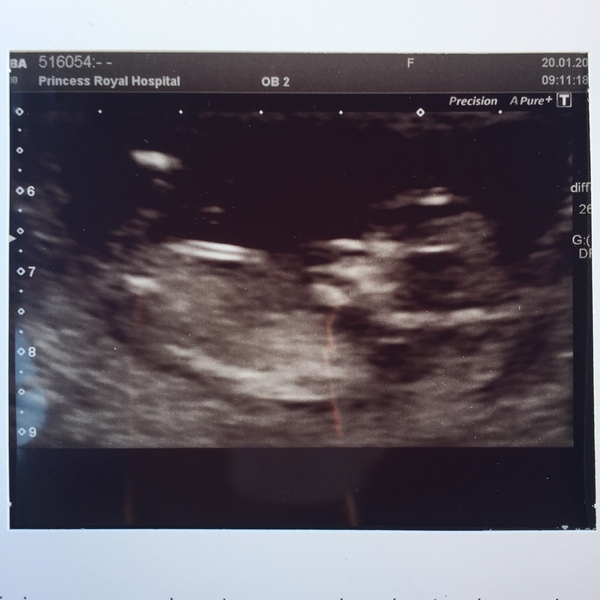

Our first scan. Any guesses on the sex?? :)

First scan